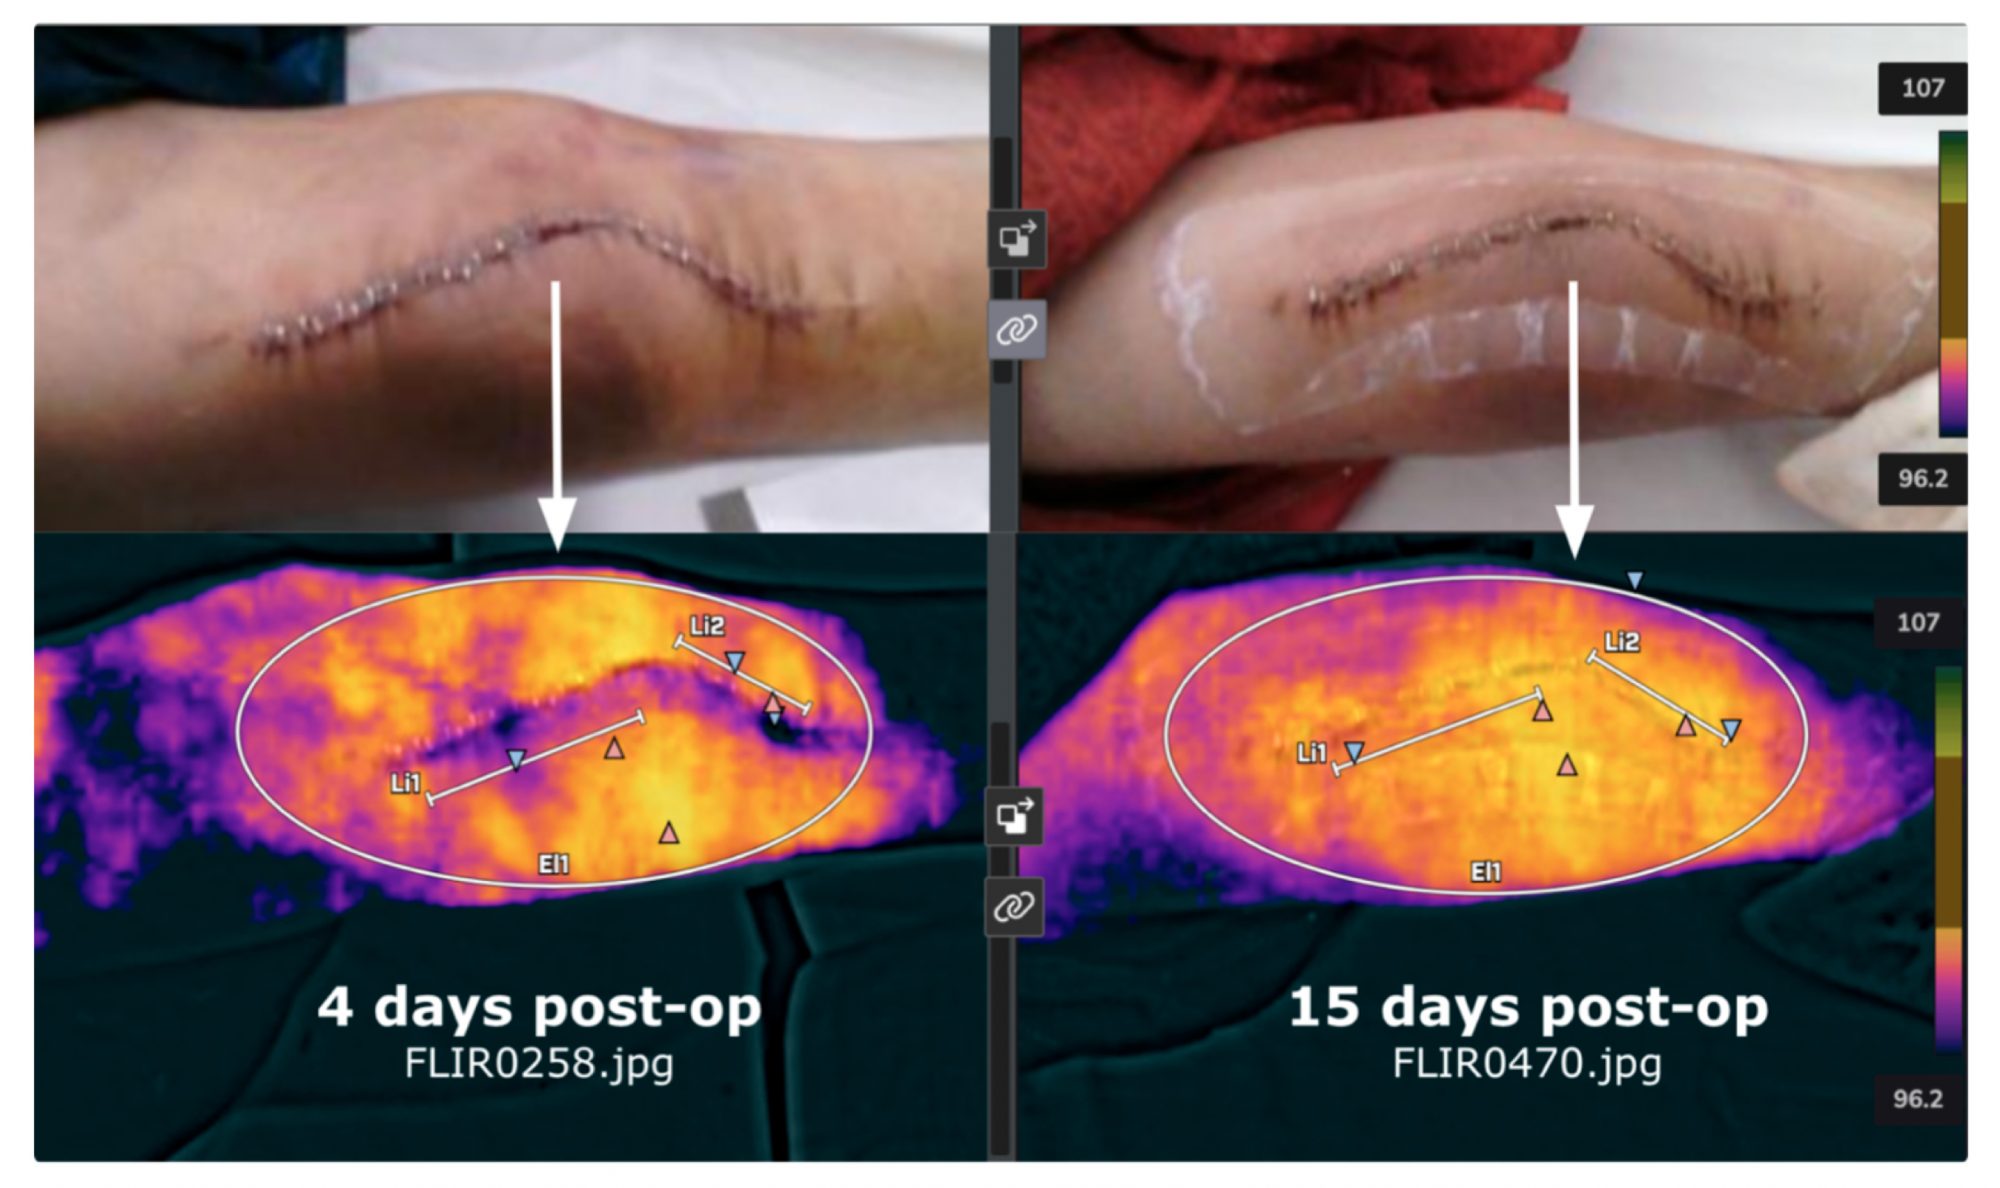

Lastly, Professor Webster is also involved in a company called Truss Health which is using AI and digital health to gather thermal scans from patients after implant surgery to predict implant success or failure. Shown in Figure 5 are thermal scans from a patient who recently received a knee implant.

Thermal scans were used to assess whether infection and/or chronic inflammation are setting in since both implant failure modes will increase local temperature. Such approaches can also be helpful to assess when staples should be removed as the temperature profile should return to normal, indicating healthy tissue.